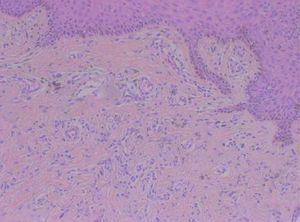

Se realizaron dos biopsias con un intervalo de un año, y ambas mostraban cambios similares, consistentes en neoformación de vasos en la dermis papilar y media, unos de morfología capilar y otros en forma de hendidura (fig. 2). Las células endoteliales que tapizaban los vasos no mostraban atipias y existía una extravasación de eritrocitos y macrófagos, con depósitos de hemosiderina en la dermis e infiltrado inflamatorio de linfocitos, histiocitos, eosinófilos y algunas células plasmáticas (fig. 3). El CD34 fue positivo en las células endoteliales, pero negativo en las células perivasculares. La expresión de ADN del herpesvirus 8 humano (HHV-8) fue negativa.

Figura 3. Células endoteliales prominentes y depósitos de hemosiderina. Infiltrado inflamatorio de linfocitos, eosinófilos, células plasmáticas e histiocitos. Hematoxilina-eosina, x200.